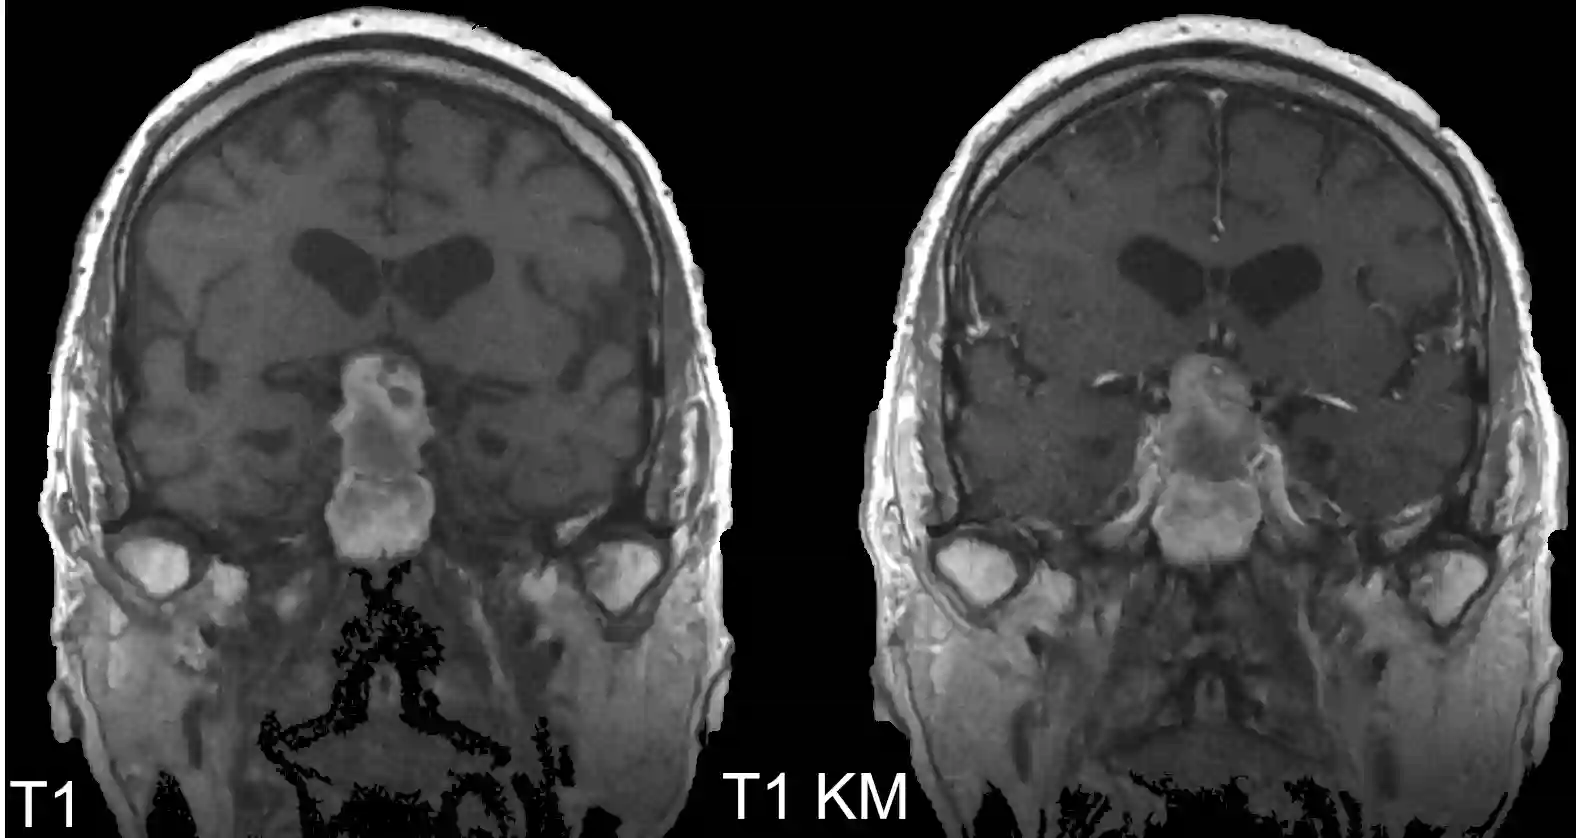

Bildgebung

MRT

Der Goldstandard zur bildgebenden Diagnostik von Hypophysenadenome ist die MRT Bildgebung.